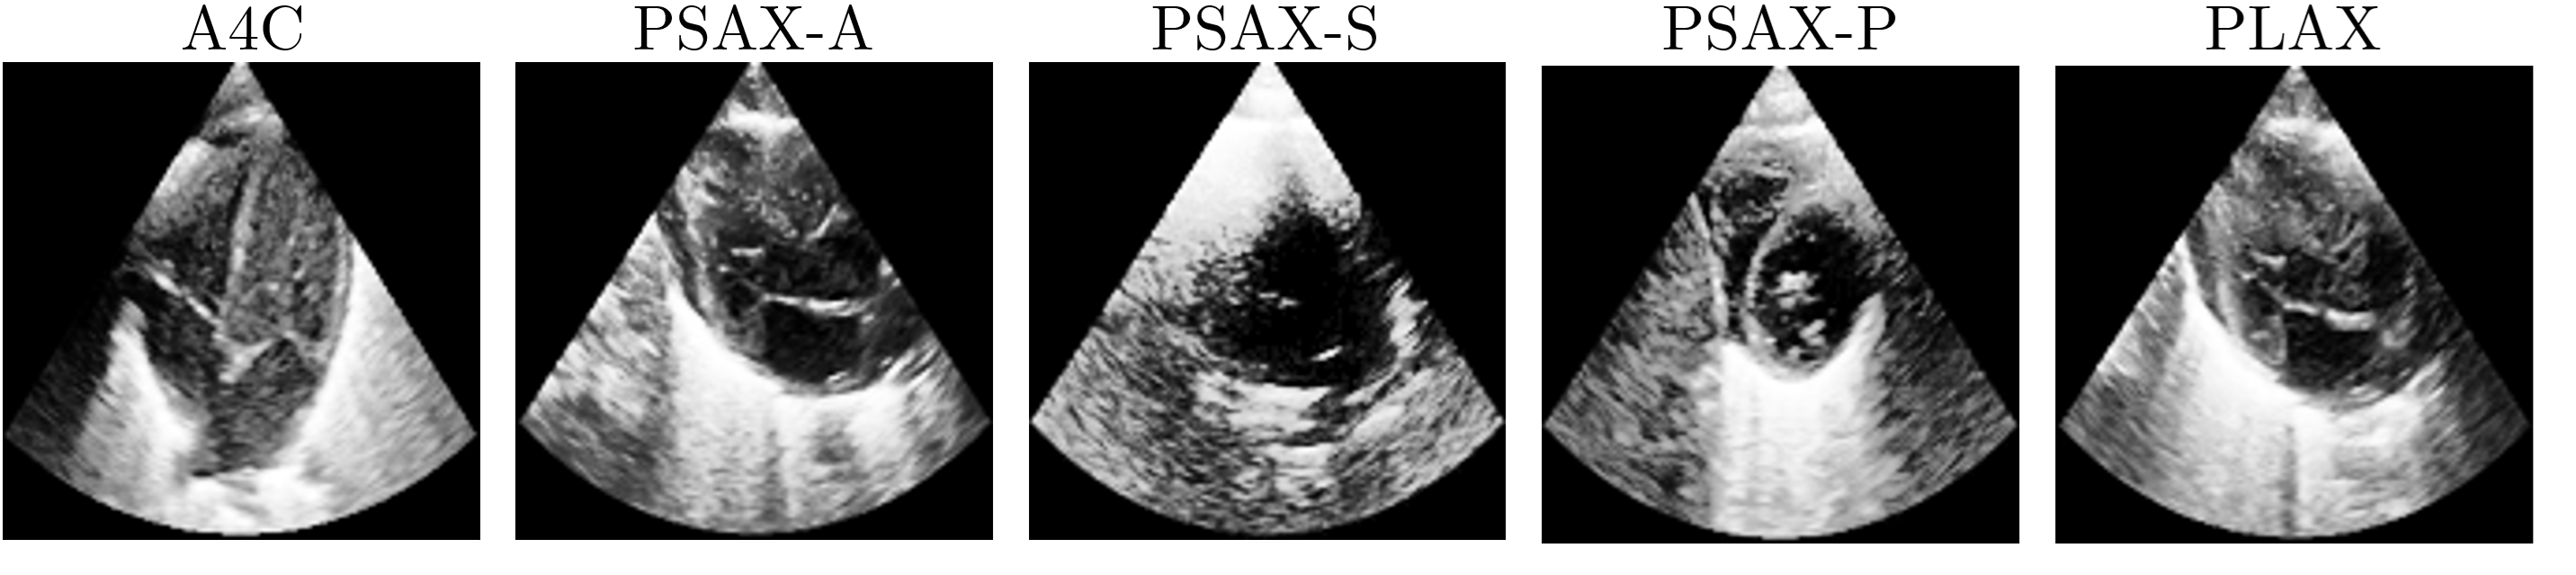

The dataset used in this work is the same as in Ragnarsdottir et al. (2024). It includes 936 transthoracic echocardiography videos collected from 192 newborns between 2019 and 2020,which are used for training and validation. Additionally, a held-out test set includes 375 videos from 78 newborns collected in 2022. All data were collected from a single medical center. A senior pediatric cardiologist performed the echocardiograms using a GE Logic S8 ultrasound machine with an S4-10 transducer operating at 6 MHz. Each video captures one of five standard heart views: PLAX (parasternal long axis), A4C (apical four-chamber), and three parasternal short-axis views—PSAX-P (papillary muscles), PSAX-S (semilunar valves), and PSAX-A (apical). Videos were recorded at 25 fps, with an average duration of 5 seconds, covering approximately 10 heartbeats.

PH severity was labeled through expert assessment and categorized into three classes: none, mild, and moderate-to-severe. The dataset distribution varies between the two sets, with the training and validation set consisting of 65% no PH, 17% mild PH, and 18% moderate-to-severe PH cases, while the test set contains 70% no PH, 12% mild PH, and 18% moderate-to-severe PH. PH grading was determined based on the PSAX-P view, where no PH corresponds to the absence of septal flattening, mild PH is characterized by septal flattening into the right ventricle, and moderate-to-severe PH is identified by septal bowing into the left ventricle. Each video is also labeled by view. Figure 1 shows an example of the five views at a fixed frame for the same patient.

Refer to caption

Figure 1: Example frames from the five standard echocardiographic views used in this study. Each row corresponds to a different view: PLAX (parasternal long axis), A4C (apical four-chamber), PSAX-P (parasternal short-axis at the papillary muscles), PSAX-S (parasternal short-axis at the semilunar valves), and PSAX-A (parasternal short-axis at the apex).